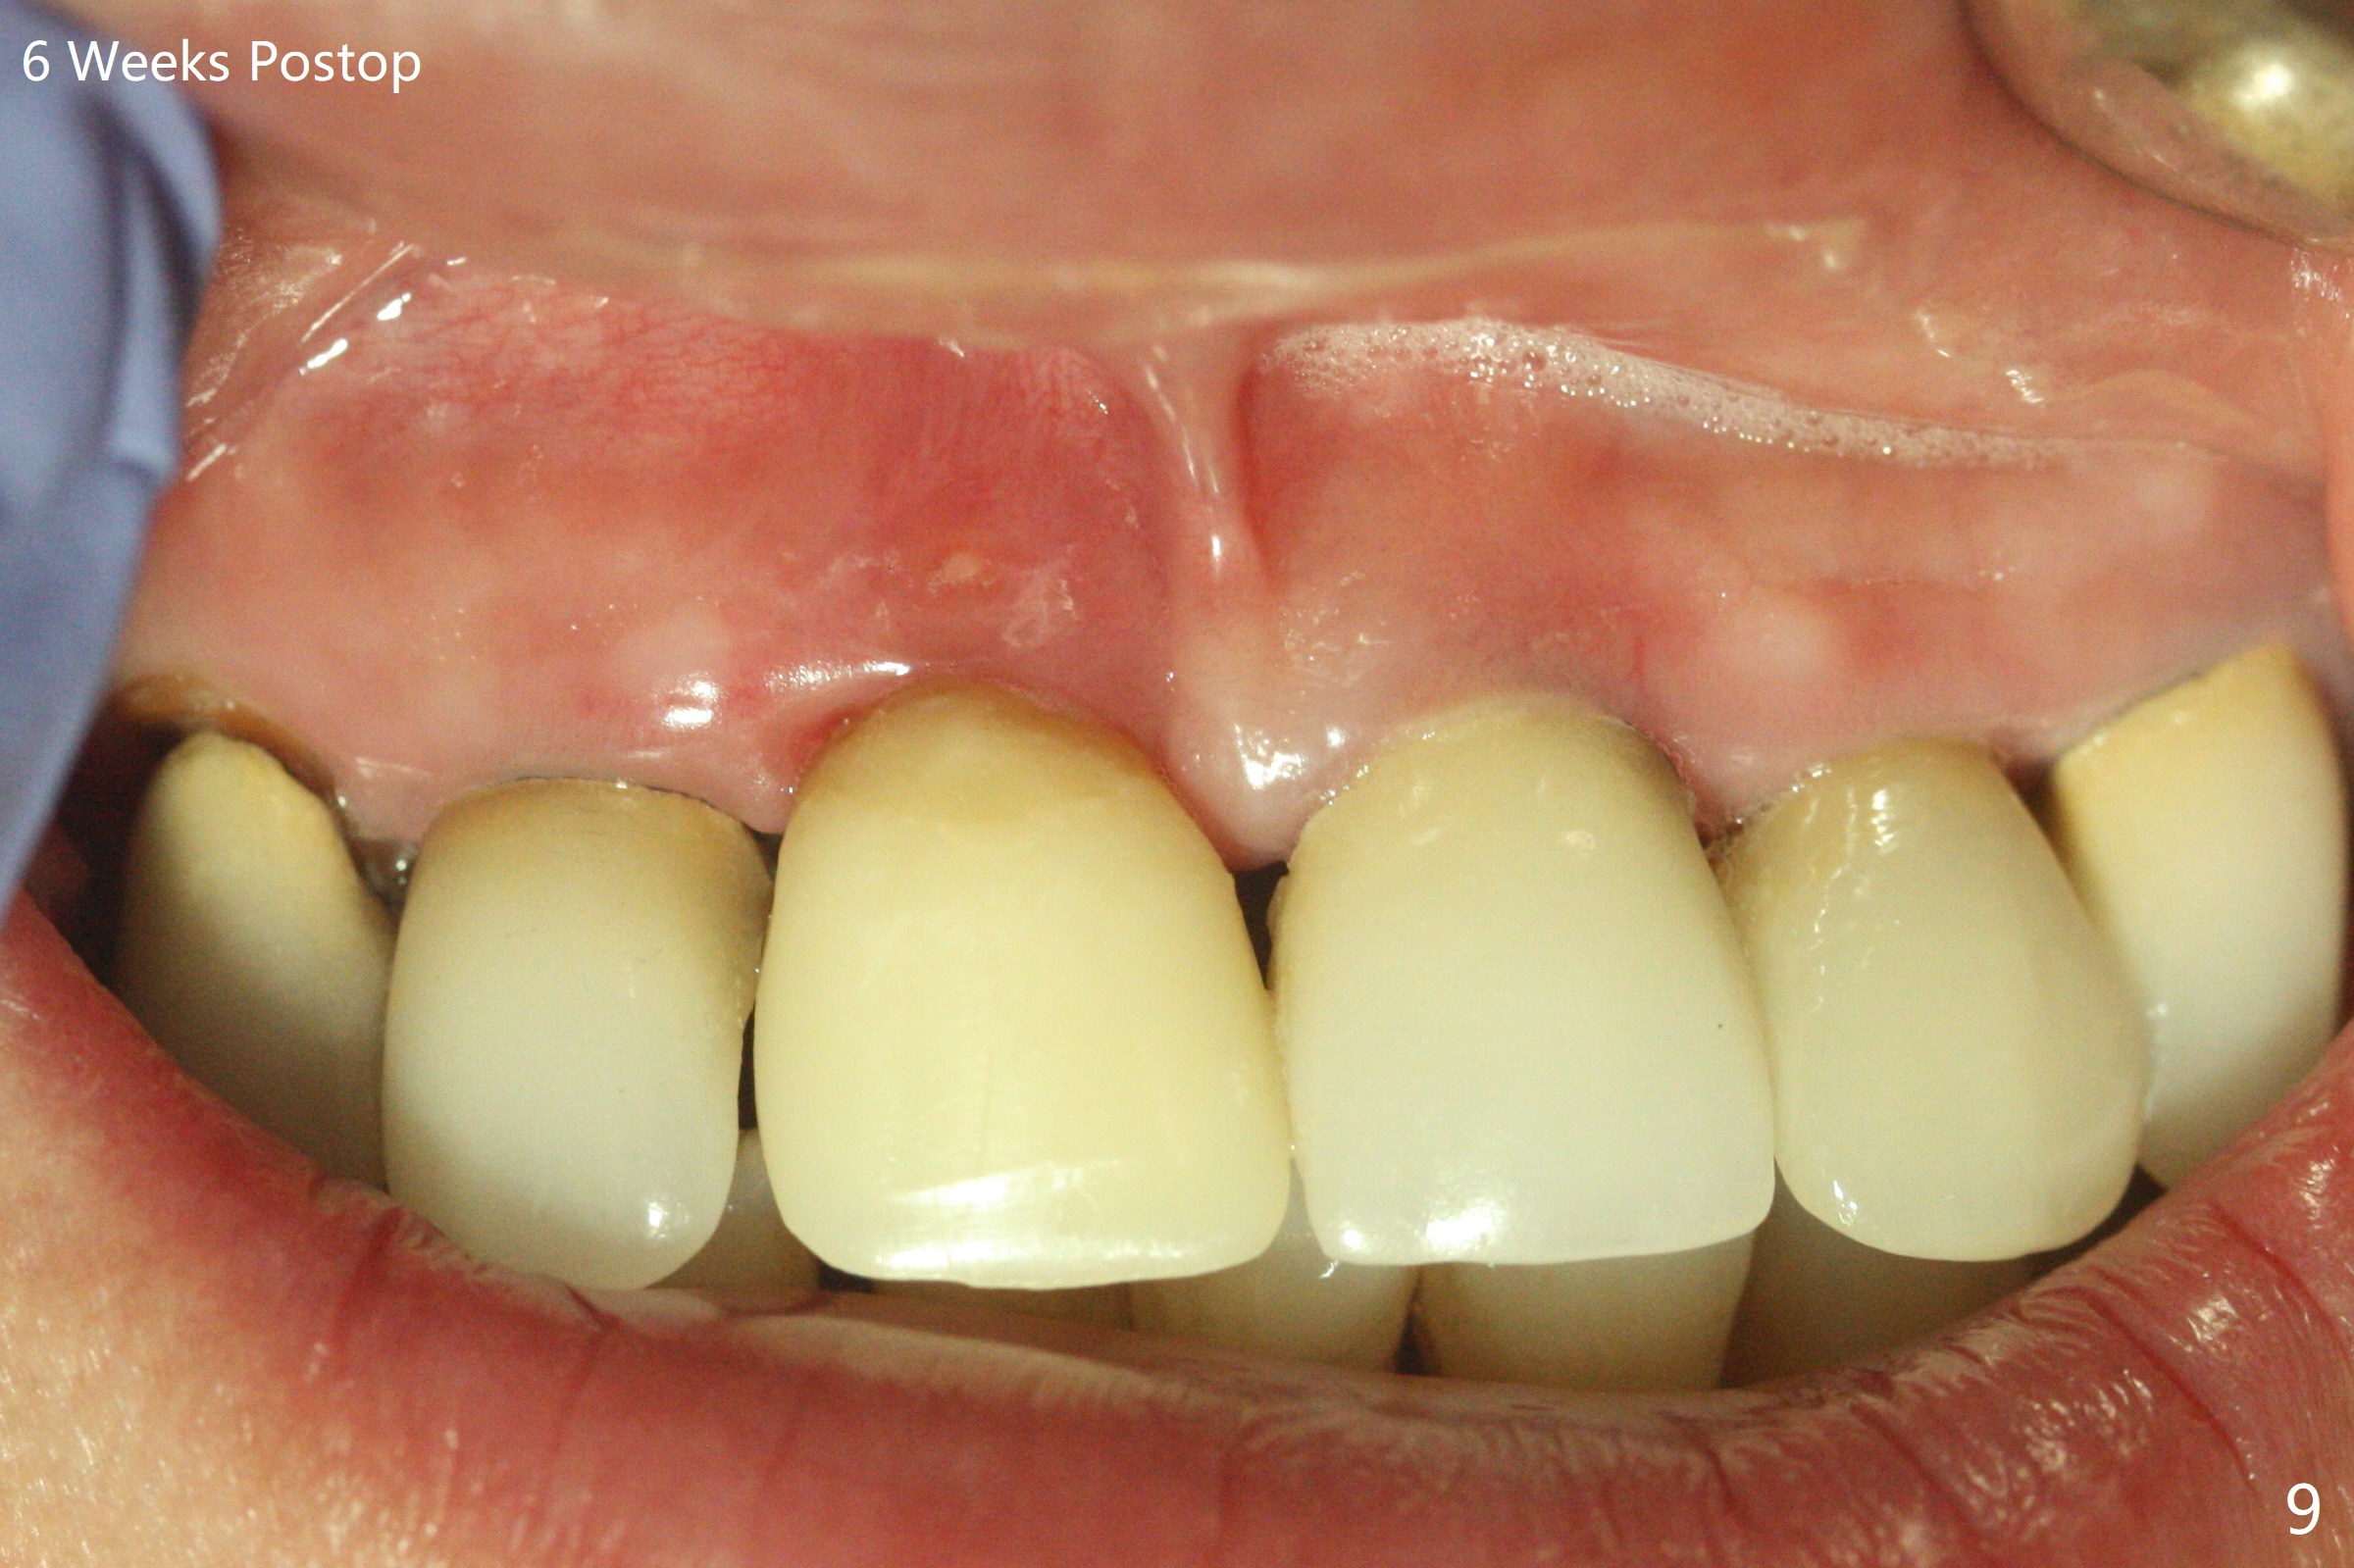

徒手初步钻洞显示方位不对(图一),重新钻洞方位尚可,好像接近鼻底(图二:红线);植入3x11.5毫米一段式植体(图三),3-5个螺纹暴露,植体似乎接近鼻底;旋转植体三趟,植体仿佛卡人鼻底,扭力大约35Ncm,植入粘性骨粉(图四,五:*)前,塞入PRF膜,紧贴颊侧粘膜,促进瘘道愈合。骨粉不仅围绕植体,而且紧贴邻牙牙根(图六(第二轮植骨:overgrafting):<)。病人术后第二周开始使用水牙线,术后三周牙龈健康多了,瘘道消失(图七)。术后六周颊侧骨壁开始塌陷(图八:>),临时牙冠颊侧颈部显得隆起(*)。调整后,牙冠外形改善(图十一至十三),取模前颊侧牙龈缘有可能下降,两个中切牙龈缘可能一致。术后3.5个月骨粉形态(图十四)与术后即刻(图六)有所不同。颊侧牙龈仍红肿轻度触痛(图十五),可能因为临时牙冠不利于局部卫生,所以决定取模制作永久性牙冠。粘固时使用临时胶水,并且涂抗菌素。另外一个可能因素是颊侧骨板薄(图十六:*),细菌感染植体螺纹,永久性牙冠粘固前,拍摄CT(放置cotton roll),必要时,植骨。永久性牙冠远中有缝隙,为了预防病人后悔,使用临时性粘固剂固定(图十七)。Return to No Caries DIO 下一个病例 一段式植体边缘制备 导板与内提升 Xin Wei, DDS, PhD, MS 1st edition 12/22/2020, last revision 06/15/2021